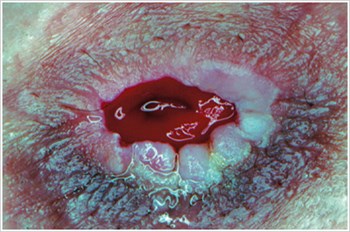

Pyoderma Gangrenosum3

Description/Causes:

An inflammatory skin disease often seen in patients with inflammatory bowel disease ( IBD ) such as Crohn's disease or ulcerative colitis.

Symptoms:

- Irregularly shaped, red, painful, infected ulcers, with red-to-purple rolled margins; appear on legs, buttocks, face, and peristomal area.